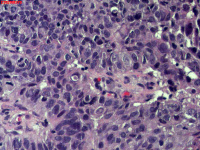

性别

男

年龄

40岁

临床诊断

肺癌?

一般病史

增强CT提示右肺中叶粘液栓;气管镜见右肺中叶外侧段新生物,考虑恶性可能。

图1

鳞状细胞癌